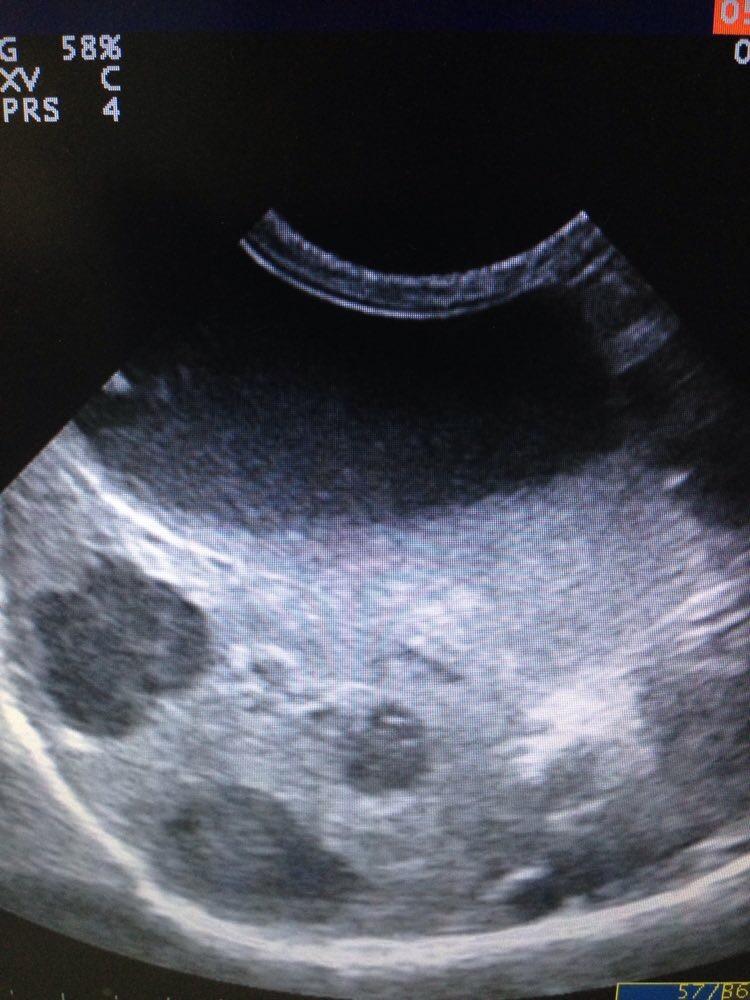

US findings: small pools of free fluid, not possible to sample. Gastric wall thickened, with mixed echogenicity, loss of detail, muscularis and serosa is intact in certain areas. Pyloric appears more normal and lesions seem to extend from fundus to Antrum. Regional LNs are enlarged and some of them very much abnormal in size shape and echostructure. Liver appears diffusely hyperexhoic with 3 focal hypoechoic areas, portal and hepatic veins dilation, GB dissension with abundant sludge and pancreatic region practically unrecognizable; I could not really visualize pancreas. Both adrenals are normal. Kidneys both in close contact with abnormal liver and Ln in right and left quadrants respectively and cranial poles Cortexes appear irregular in echogenicity. Intestines appear to have a good motility and no abnormal layering seen. Oleo exam junction not visualized…

Any ideas? It looks very much like neoplasia to me… So I did FNA but owner didn’t want to sedate and dog only allowed 2 needles. Gastric thickened mucosa is what I got, by the time I wanted to access LNs dog wouldn’t cooperate anymore. My question is… Next time, do I still try and get aspirate from gastric mucosa? Or try some other tissue? I would have chosen LNs first but I didn’t manage to get them superficially accessible after this picture was taken.